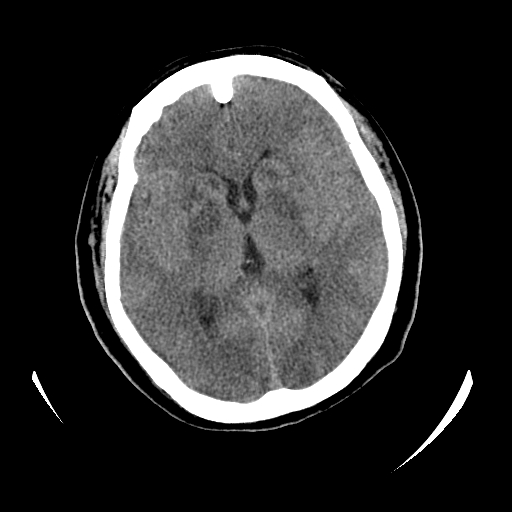

女,53岁,发现昏迷1天,血压不高,有精神病史。临床诊断:脑梗死?

ct诊断:1、双侧基底节区对称性脑梗塞。

2、双侧额叶、枕叶广泛密度减低,考虑缺血梗塞可能性大。

3、脑池小,脑沟浅,提示颅内高压。

测左枕叶白质ct值 约22hu 。请各位老师给出恬当诊断。

征象:病变呈对称性分布于双侧大脑半球,累及范围广泛,白质较灰质密度减低更为明显;脑沟变浅,脑池变窄;

缺氧性脑梗死的影像表现比较特殊:

由于苍白球对血供的敏感度较高,故较早受累;其它的表现有分水岭区脑梗死等;

双侧环池,四叠体池显示模糊,原因?建议增强